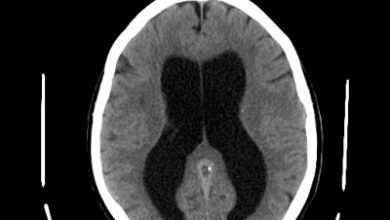

Ultrazvuk mozga novorođenčeta

Ultrazvuk mozga novorođenčeta ne spada u standardne preglede koji se rade nakon što se beba rodi, već samo ako za…